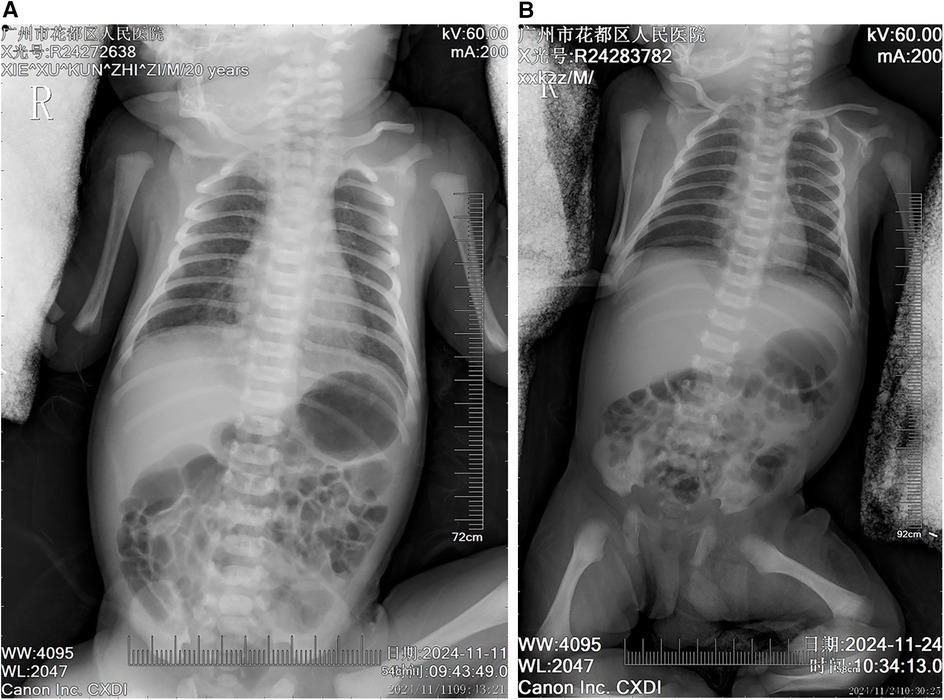

The patient, a neonate, was admitted to the Department of Neonatology at 06:37 on November 11, 2024, due to “grade III meconium-stained amniotic fluid, and tachypnea and rales for over an hour after birth.” Upon admission, based on the grade III meconium-stained amniotic fluid and postnatal respiratory distress, a preliminary diagnosis of meconium aspiration syndrome (MAS) was made, and caput succedaneum was noted. Chest x-ray (Figure 1A) revealed increased and thickened bilateral lung markings, with patchy, ill-defined opacities in the lung fields, predominantly in the right lower lobe, suggestive of neonatal aspiration pneumonia. Cardiac ultrasound demonstrated a patent foramen ovale (PFO, 2.9 mm) and mild tricuspid regurgitation, with no other significant structural cardiac abnormalities detected. Initial laboratory investigations indicated coagulopathy, evidenced by elevated D-dimer (2,280.46 ng/mL), decreased fibrinogen (1.53 g/L), prolonged prothrombin time (PT 18.8 s), prolonged activated partial thromboplastin time (APTT 55.1 s), and metabolic acidosis (pH 7.314, lactate 4.80 mmol/L). Initial treatment included intravenous penicillin (50,000 units/kg every 12 h) for empirical coverage of common neonatal bacterial infections, oxygen supplementation to maintain SpO₂ > 90%, intravenous infusion of 10% glucose solution for blood glucose stabilization, and a single intramuscular injection of vitamin K1 1 mg for prophylaxis against hemorrhagic disease of the newborn. Supportive care and close monitoring were prioritized given diagnostic uncertainty on day 1.

Figure 1. Chest radiographic changes in a neonate with meconium aspiration syndrome before and after treatment (A) initial chest radiograph (day 0 of life) showing diffuse bilateral pulmonary infiltrates with hyperinflation, patchy opacities, and flattened diaphragm consistent with meconium aspiration syndrome. Note the increased lung markings and coarse reticular pattern throughout both lung fields. (B) Follow-up chest radiograph (day 14 of treatment) demonstrating significant improvement in pulmonary aeration with resolution of the diffuse infiltrates. The lung fields appear clearer with normal lung volumes and diaphragmatic contour, indicating successful response to respiratory support and antimicrobial therapy.

November 24, 2024

On the 14th day of hospitalization, the patient's condition significantly improved. Repeat chest x-ray (Figure 1B) showed near resolution of bilateral pneumonia. Laboratory investigations revealed a marked decrease in inflammatory markers, with CRP decreasing to 0.25 mg/L, WBC to 13.19 × 10⁹/L, D-dimer to 973.79 ng/mL, and platelet count recovering to 140 × 10⁹/L. Repeat arterial blood gas analysis demonstrated normalization of acid-base balance (pH 7.35, partial pressure of carbon dioxide 34.70 mmHg, base excess −1.6 mmol/L), good oxygenation (partial pressure of oxygen 75.20 mmHg), and normalization of lactate levels (2.10 mmol/L). With comprehensive assessment indicating clinical improvement, penicillin and azithromycin were discontinued, and low-flow oxygen (1l/min) and nutritional support were continued, along with close monitoring of respiratory status, jaundice levels, and platelet count. No bleeding manifestations or hemodynamic instability were observed prior to discharge.